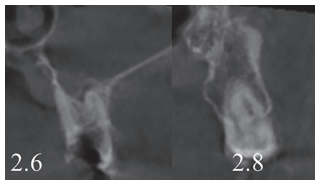

En la exploración radiográfica, mediante radiografía panorámica, se apreciaron ambos terceros molares inferiores retenidos, en posición horizontal (Figura 3), e imágenes radiolúcidas apicales en posición de 2.6 y 4.6. En el escáner de haz cónico se evaluó la morfología radicular del tercer molar superior izquierdo, y la dimensión de la lesión radiolúcida apical del primer molar superior izquierdo (Figura 4), datos necesarios para valorar el grado de adaptación del diente donante en el lecho receptor.

Se planificó la exodoncia del 4.6 y 2.6, y el legrado de los procesos apicales, y se le sugirió al paciente el autotrasplante del tercer molar superior izquierdo (2.8) para sustituir el 2.6 (Figura 5).